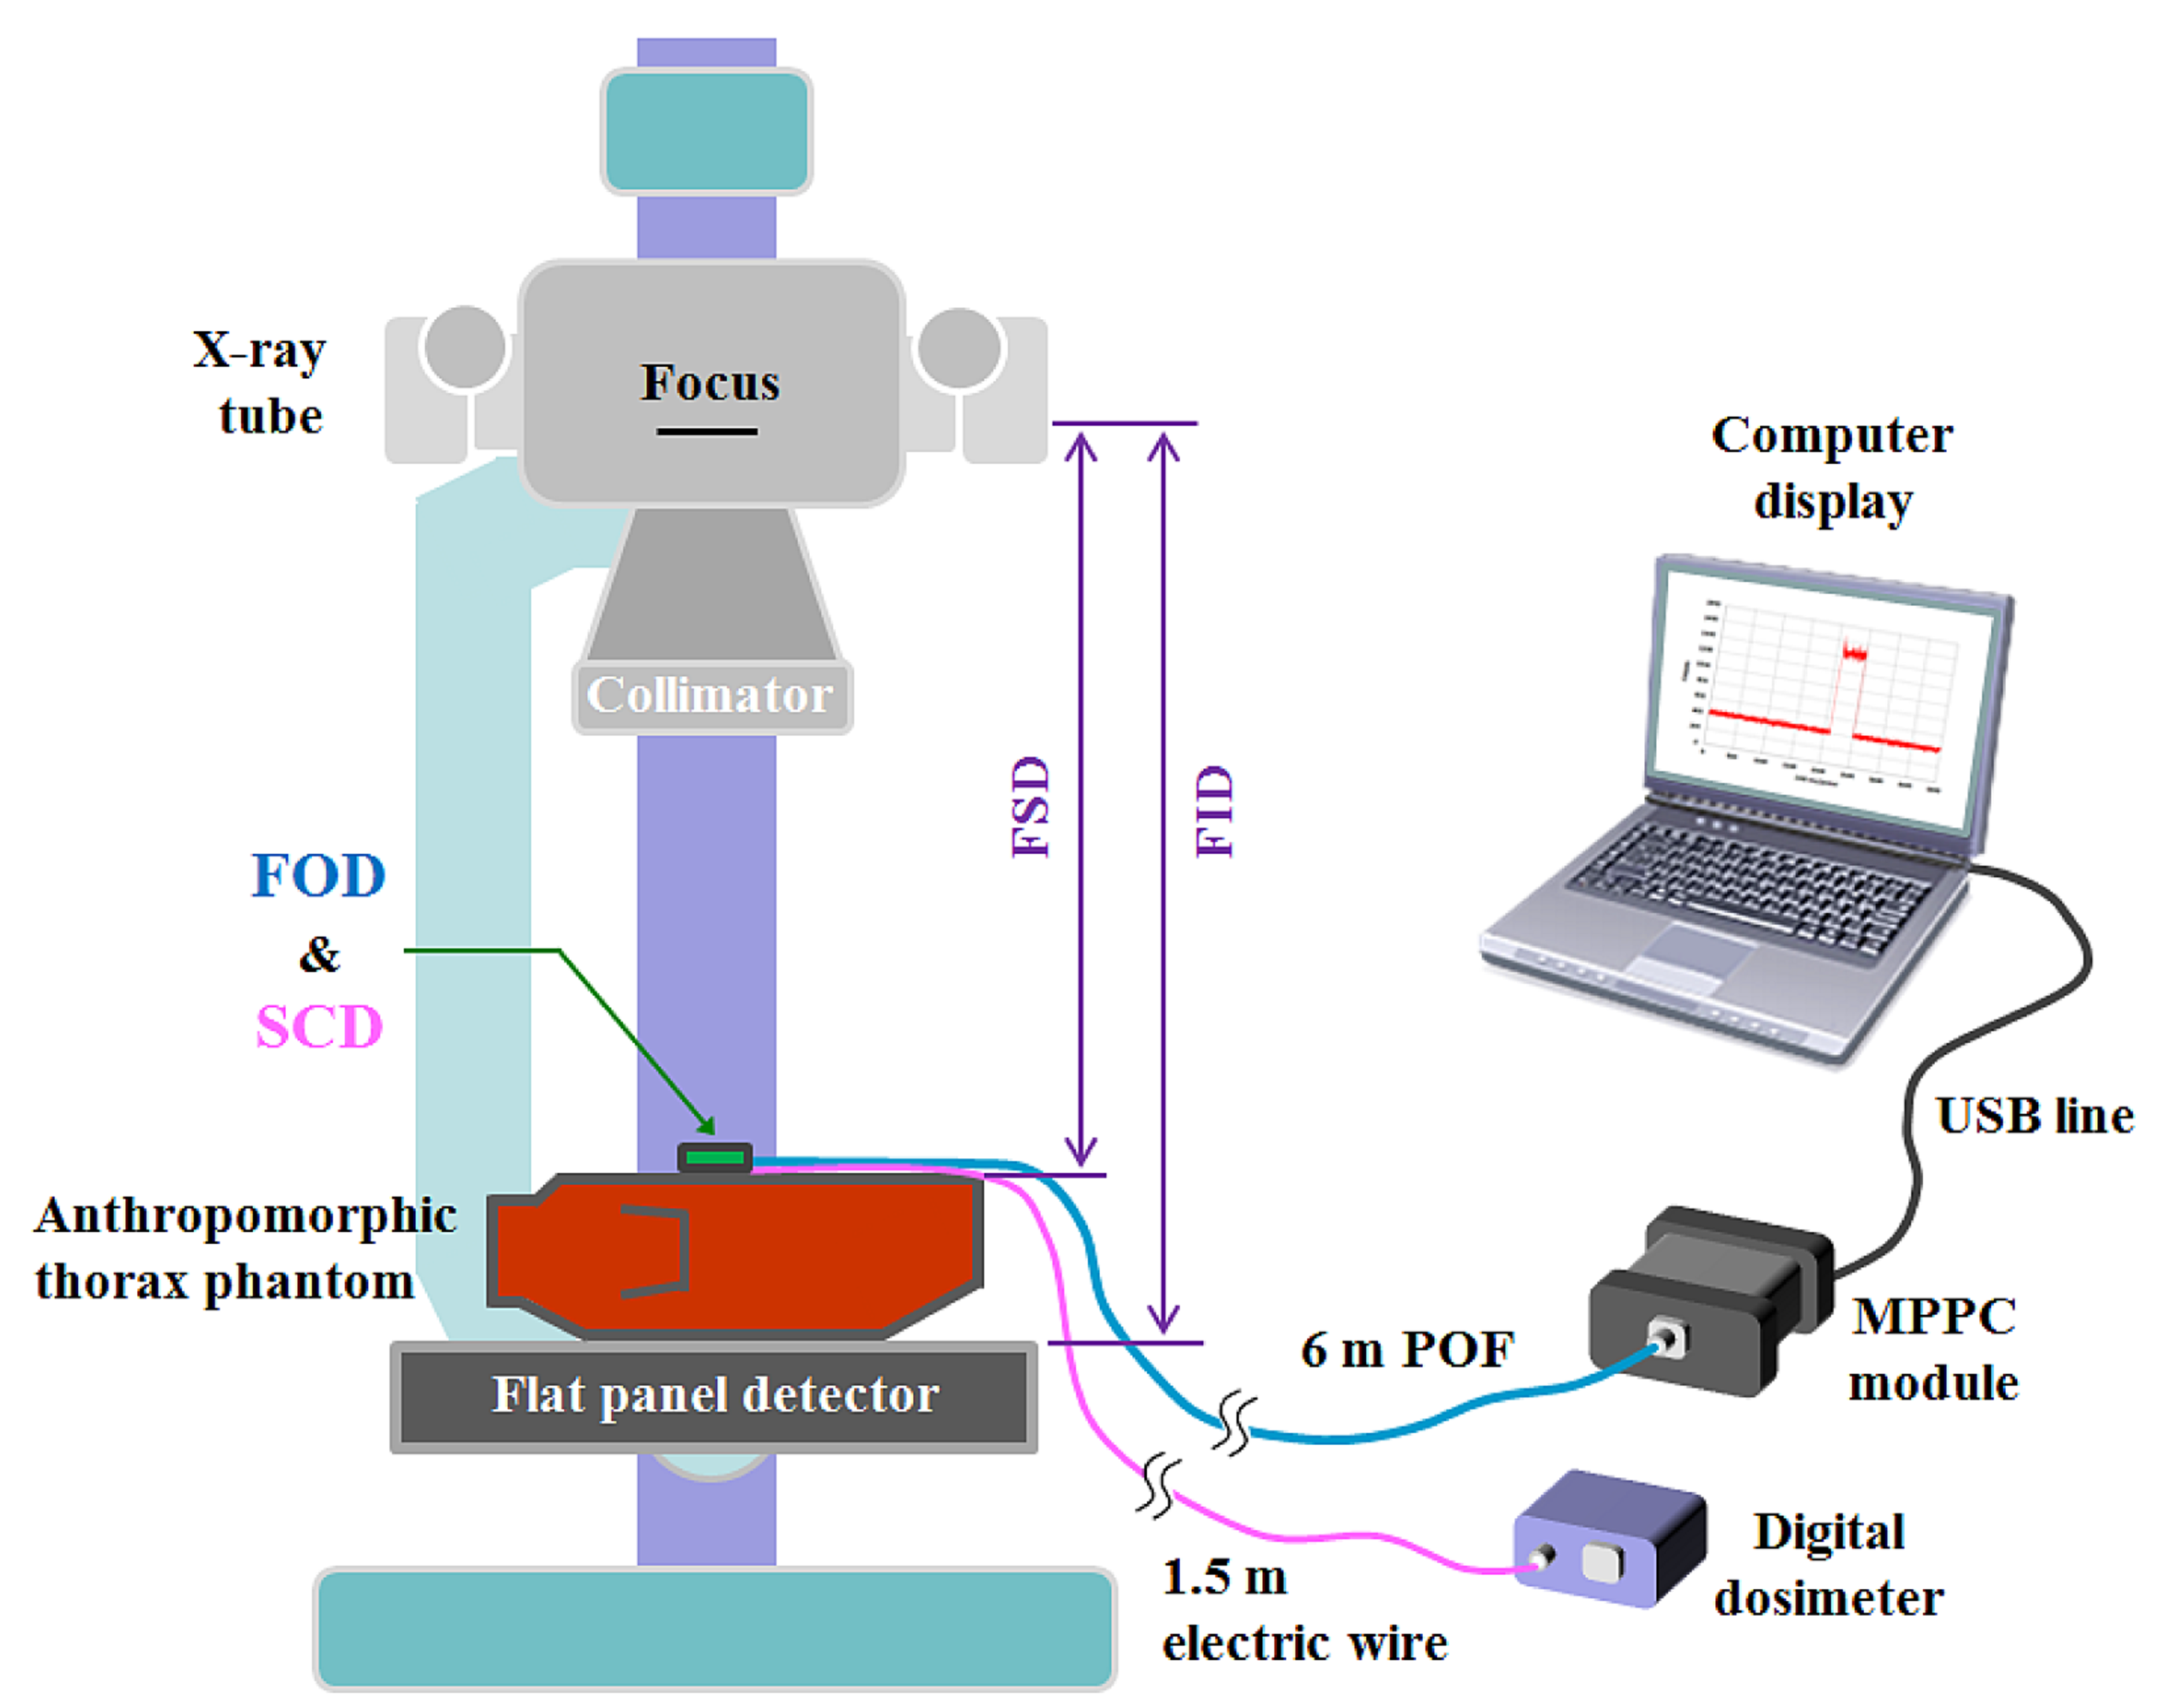

In plain radiography examinations, the patient dose is generally described as the entrance surface dose (ESD), which is measured at the center of the entrance surface in the X-ray beam field, and includes backscattered radiation from the patient [18,19]. Figure 2 shows the experimental setup for measuring ESDs in a digital radiography (DR) system using the FOD and a conventional SCD. To measure weak scintillating light transmitted from the sensing probe, we used an MPPC module (C10751-03, Hamamatsu Photonics) that has a SMA-type optical fiber adapter for fast and easy connection of an internal MPPC device (S10362-11-100U, Hamamatsu Photonics) to the sensing probe. The MPPC device with an active area of 1 × 1 mm2 is composed of multiple avalanche photodiode (APD) pixels and the signal output from the MPPC module is the total sum of the outputs from all APD pixels of the MPPC device.

The MPPC module has high sensitivity in a spectral response range from 320 to 900 nm and a peak sensitivity wavelength of 440 nm. At the threshold level condition of 0.5 photon equivalent (p.e.), the photon detection efficiency and the typical dark count of this MPPC module are 45% and 900 kilo counts per second (kcps), respectively. Here, p.e. indicates that one photon was detected. As a reference dosimeter, a commercially available SCD, a finger-shaped dose sensor that is connected to a digital dosimeter (Pehamed, ALPHA plus, Sulzbach, Germany) was used to compare its ESDs with the output signals of the FOD. To evaluate the performance of the fabricated FOD, an experiment was carried out using an X-ray tube (RotanodeTM E7252X, Toshiba Electron Tubes & Devices, Saitama, Japan) of the DR system (Clear Vision DR 7000F, JPI Healthcare, Osong, Korea) with a focal spot of 0.6/1.2 mm, a 12° rhenium-tungsten-faced molybdenum target, permanent filtration of 0.9 mm-Al at 75 kV, and a maximum tube voltage of 150 kV. In addition, we used an anthropomorphic thorax phantom (RS-111, Radiology Support Devices, Long Beach, CA, USA) to provide a backscatter medium. This phantom is made of tissue-equivalent materials and represents a thorax of an average male of 175 cm with a weight of 74 kg.

Through random and repeated experiments to improve accuracy, we measured the scintillating light in order to obtain the dose value, which changed with variations of the exposure parameters, such as the tube potential (kVp), current-time product (mAs), and focus-to-surface distance (FSD) or focus-to-image receptor (i.e., the flat panel detector of the DR system) distance (FID). The scintillation output signals of the FOD were then compared with the dose values simultaneously obtained using the SCD. For this experiment, the values of the tube potential, current-time product (tube current × irradiation time), FSD, and field size were fixed at 100 kVp, 5 mAs (50 mA × 100 ms), 85 cm, and 30 × 30 cm2, respectively. During X-ray irradiation, the SCD was placed alongside the sensing probe of the FOD. Error bars were drawn on all data points in the figures showing the experimental results; however, most error bars were within the data points because they were too small to be displayed.